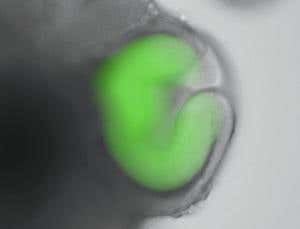

The self-organised optic cup: the retinal tissue is shown in green (Image: M. Eiraku and Y.Sasai at RIKEN Center for Developmental Biology)

Over 12 days, the retinal cells formed a vesicle which subsequently transformed into a cup-like structure. Within this “optic cup”, six major types of retinal cells were identified. They had spontaneously arranged themselves into six different layers, mimicking those seen in the adult retina.